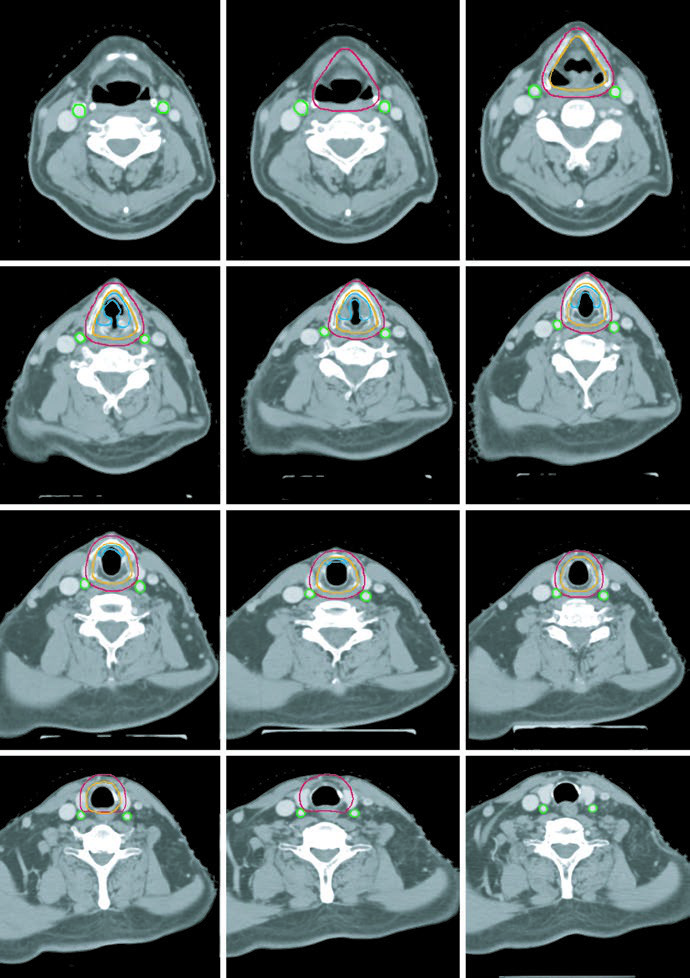

Early-stage disease: T1N0 and T2N0

For early disease, the chapter answer is direct: the CTV should encompass the entire larynx, including both commissures and the arytenoids. For T1 tumors, coverage extends from the bottom of the thyroid notch to the bottom of the cricoid cartilage. For T2 tumors, it extends inferiorly to the first tracheal ring. The inferior edge matters because many recurrences tend to track downward. In selected cases, the ipsilateral cord can be considered.

For early glottic cancer, carotid-sparing IMRT should be considered, although a CT-based opposed lateral technique remains acceptable. With laterals, the superior border reaches the bottom of the hyoid or the top of the thyroid notch, the inferior border reaches the bottom of the cricoid cartilage, the posterior border is the anterior edge of the vertebral bodies, and 1 cm of anterior flash is recommended. Beams may need a 5-10° inferior angle to clear the shoulders, and 15-30° wedges are often used to maintain dose homogeneity.

Dose is also stage-specific. T1N0 glottic tumors are treated to 63 Gy in 28 fractions because randomized data support better local control with 2.25 Gy per fraction. T2N0 glottic tumors benefit from doses above 65 Gy and fraction size of at least 2.25 Gy, so the described regimen is 65.25 Gy in 29 fractions. In selected cases, chemoradiotherapy may be reasonable.

The final planning notes are concise and useful: a PTV margin of 0.3-0.5 cm may be used depending on immobilization and laryngeal motion, flash and bolus should be used when the anterior commissure is involved, and heterogeneity over the larynx should be limited to 105% of prescription.